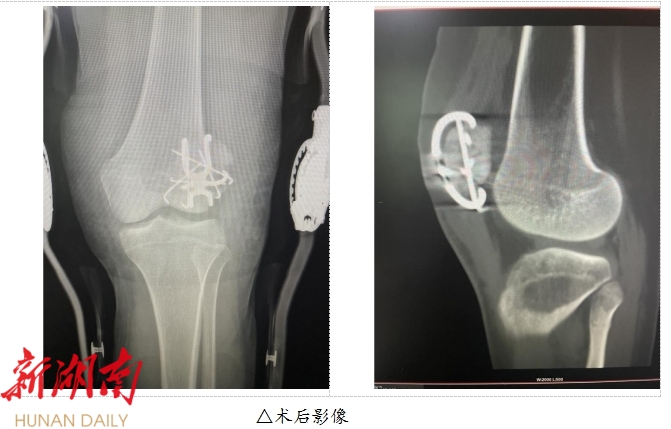

手术当天,运动医学科主任贺洪辉、副主任周淑平带领的手术团队凭借精湛的技术和丰富的经验,仅用一个多小时的时间,成功完成了修复半月板和髌韧带,复位髌骨多个骨折块,使手术顺利完成。

术后,患者在全科医护人员的精心照料下,恢复良好,现已能够下地行走。此次手术的成功,不仅得益于贺主任手术团队的高超技术,还离不开南华医院一直在细分的骨科医学团队和完善的术后康复体系。